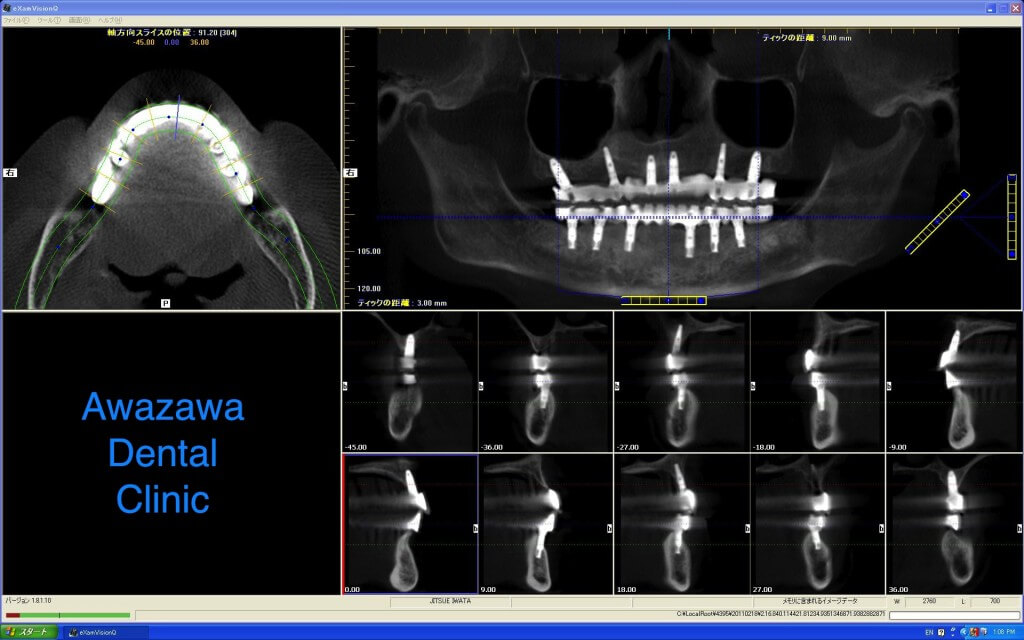

*上部構造装着3年経過後のCT画像です。シミュレーションによるインプラントの適正な配置が再現されているのが確認できます。